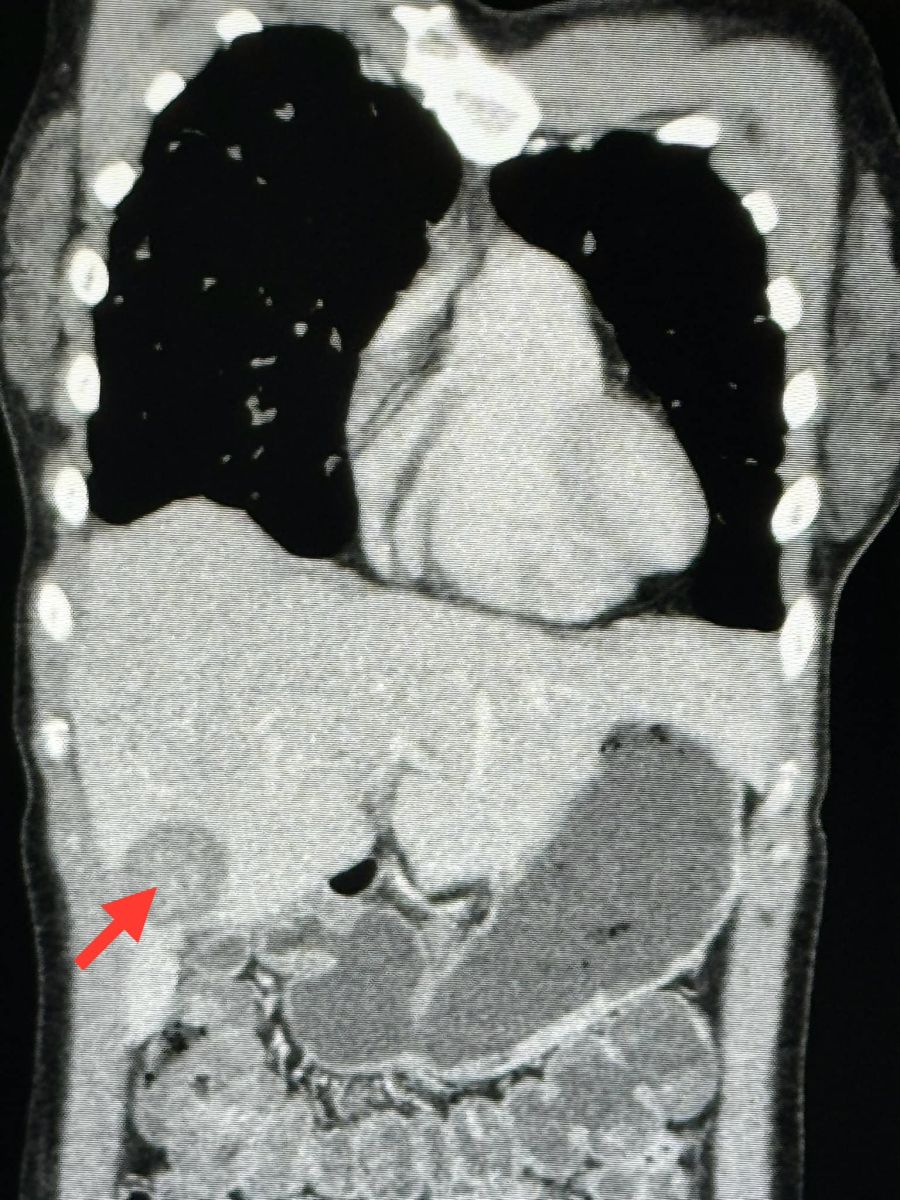

ตรวจร่างกายปกติ ฟังปอดปกติ ระดับออกซิเจนในเลือดปกติ เจาะเลือดเม็ดเลือดแดงและเกล็ดเลือดต่ำเล็กน้อย ค่าตับไต ปกติ ค่ามะเร็งทุกตัวปกติ ทำคอมพิวเตอร์ปอดและช่องท้อง พบจุดเล็กๆ ในปอดขนาด 0.8 เซนติเมตรกระจายทั่วปอด และมีก้อนในตับขนาด 3.4 เซนติเมตร ได้ทำการเจาะเนื้อในตับ ย้อมและเพาะเชื้อ ไม่พบเชื้อราและเชื้อวัณโรค ส่งชิ้นเนื้อตรวจพยาธิวิทยา พบ Epithelioid hemangioendothelioma ติดตามผู้ป่วยนับจากวันที่มีเอกซเรย์ปอดผิดปกติ ถึงปัจจุบัน 6 เดือนแล้ว ผู้ป่วยยังไม่มีอาการ